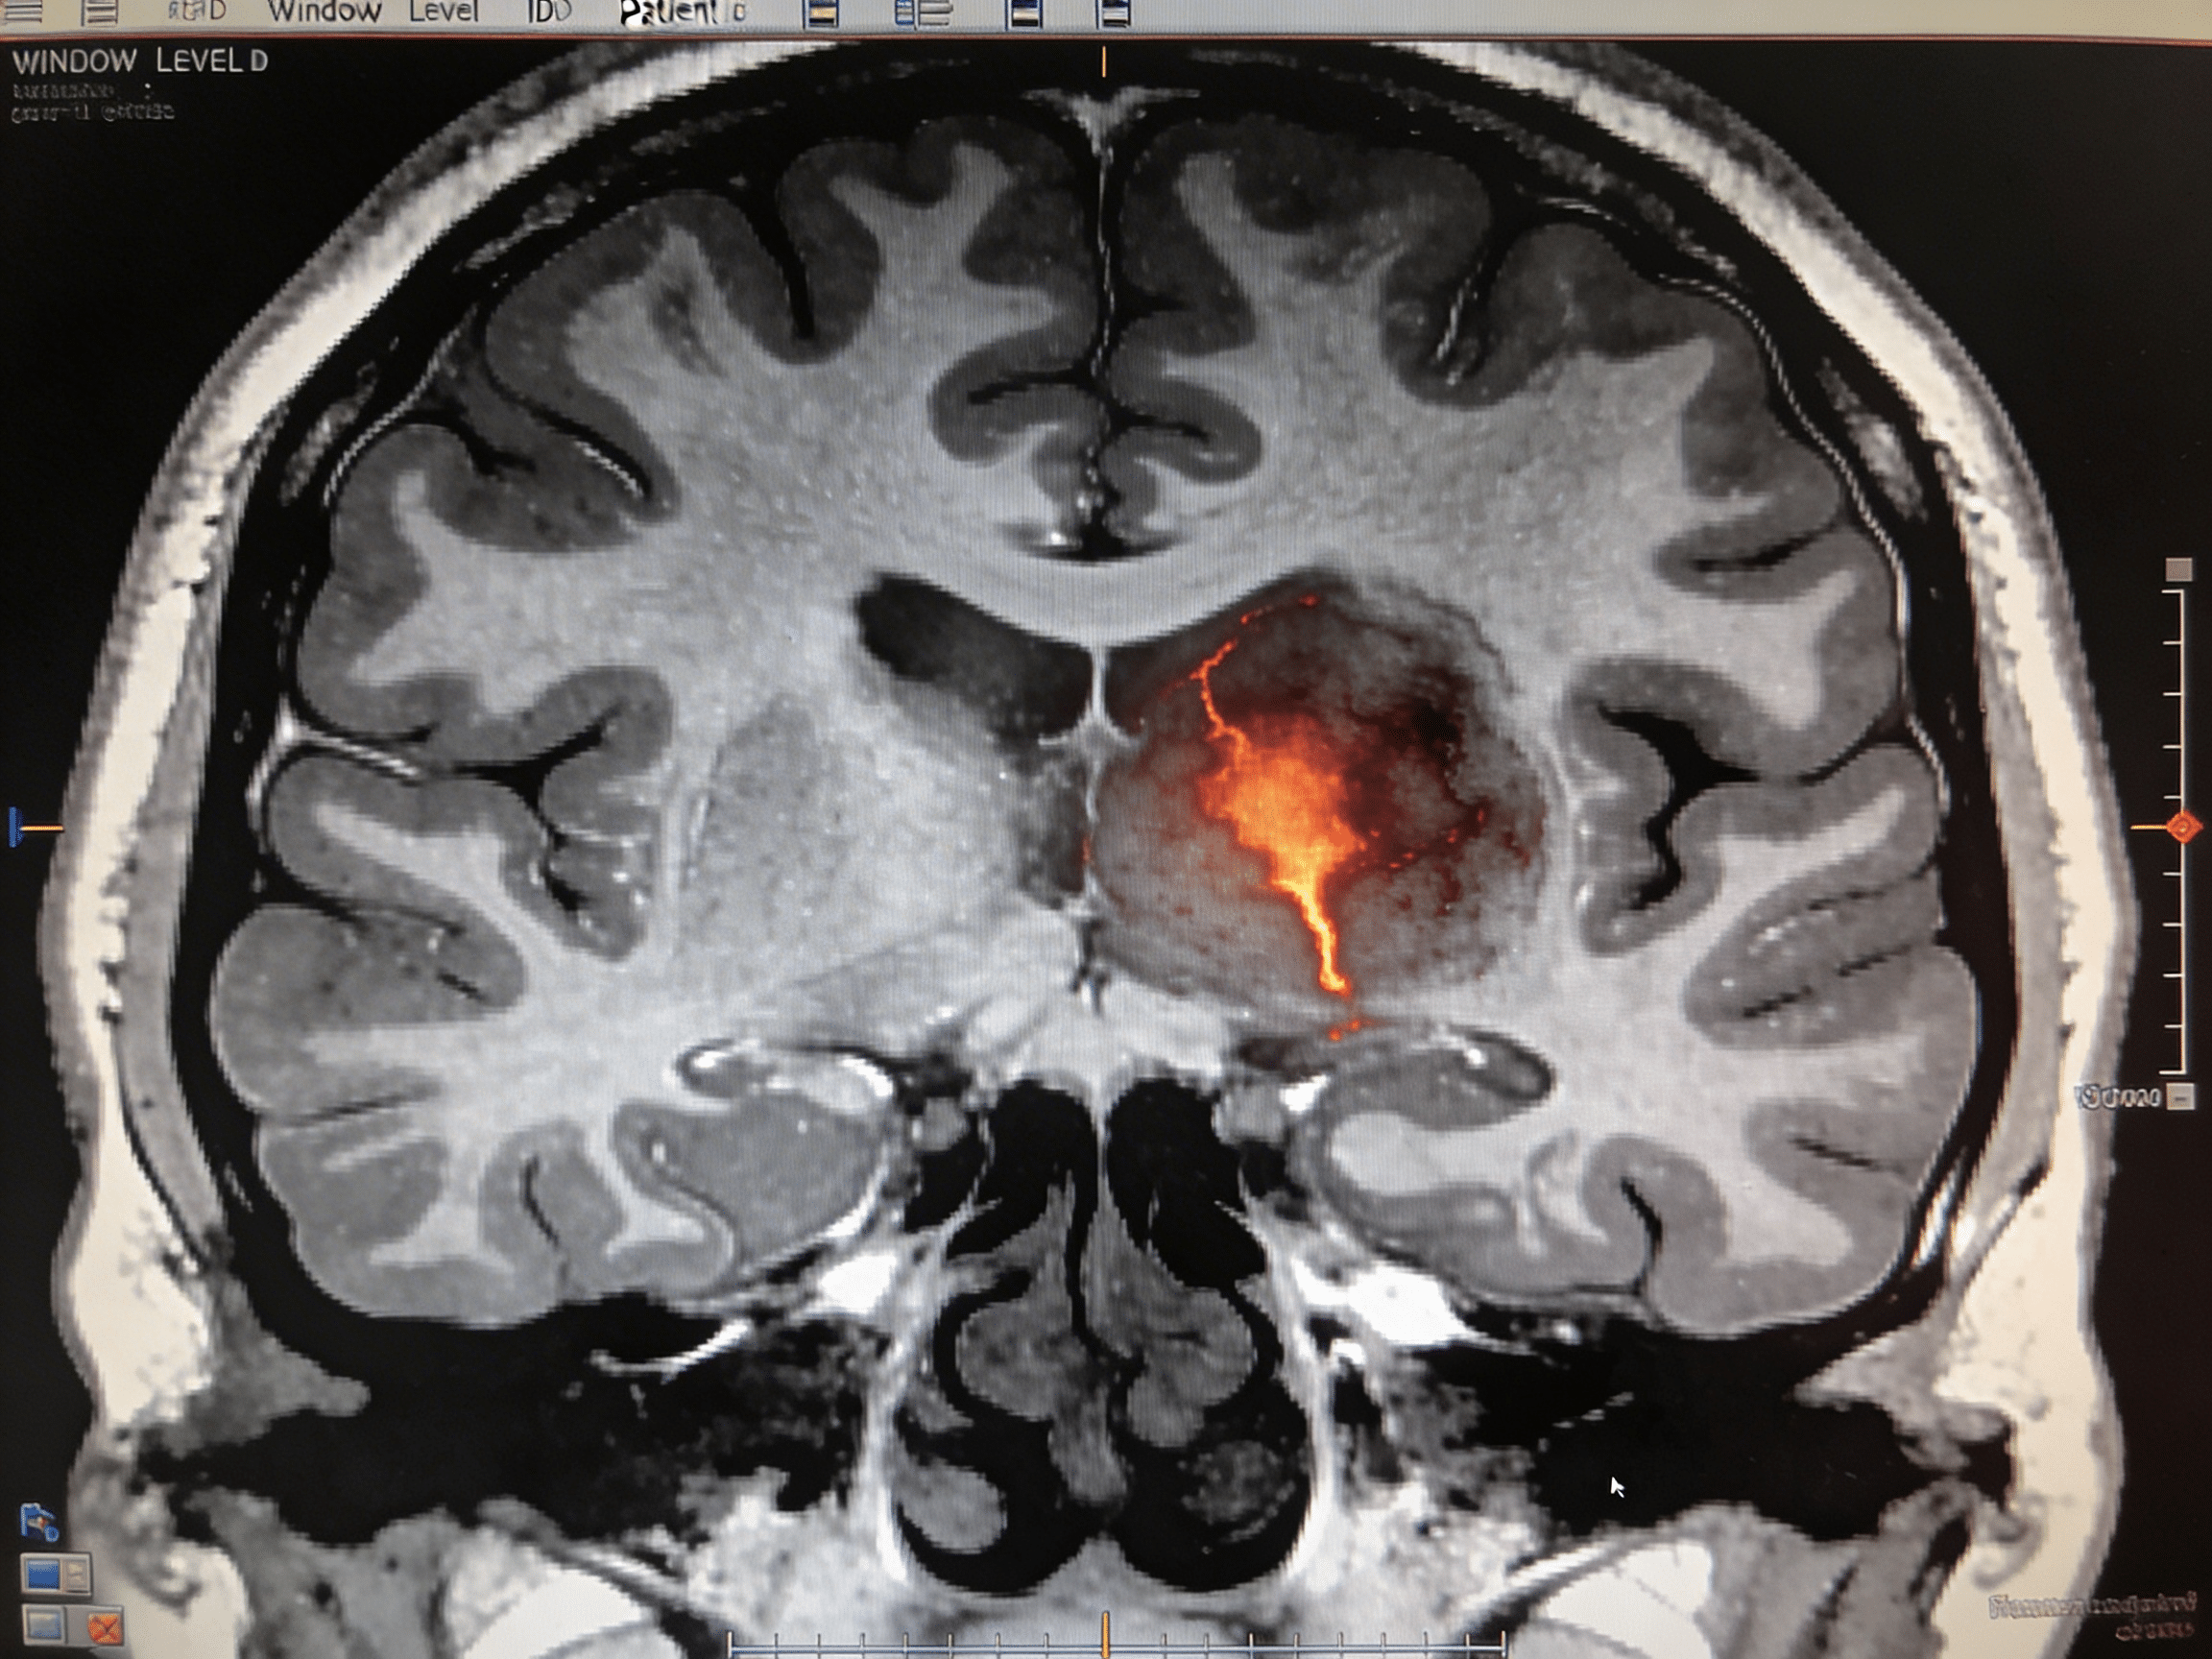

Emergency physician reviewing head CT scan at Priority ER

Board-certified emergency physicians providing immediate head CT interpretation and stroke evaluation

Priority ER's diagnostic capabilities for head CT for stroke, hemorrhage, or trauma exceed Joint Commission standards for emergency departments[14], featuring 64-slice CT scanner providing immediate high-resolution brain imaging identifying acute ischemic changes (loss of gray-white differentiation, hyperdense vessel sign), hemorrhagic stroke (hyperdense blood), skull fractures, and traumatic brain injuries within 10 minutes. Our emergency physicians trained in neuroimaging interpretation identify Alberta Stroke Program Early CT Score (ASPECTS) determining stroke severity, midline shift indicating mass effect, and hemorrhage volume calculating surgical urgency when neurosurgical intervention becomes necessary[15]. The integration of FAST (facial droop, arm weakness, speech difficulty, time) assessment, NIHSS scoring quantifying neurological deficit, and immediate treatment protocols ensures comprehensive stroke care from symptom recognition through definitive intervention.

Advanced imaging through our comprehensive diagnostic capabilities provides CT angiography visualizing arterial occlusions when mechanical thrombectomy candidates require transfer to comprehensive stroke centers, CT perfusion identifying ischemic penumbra (salvageable brain tissue) extending treatment windows beyond standard 4.5 hours, and repeat head CT performed 24 hours post-tPA monitoring for hemorrhagic transformation. For trauma patients, our emergency physicians utilize Canadian CT Head Rule and New Orleans Criteria determining which head injuries require imaging, preventing unnecessary radiation while ensuring dangerous bleeds aren't missed when clinical indicators mandate scanning. This comprehensive approach explains why the American Heart Association mandates door-to-CT time under 25 minutes for stroke patients, with Priority ER consistently achieving 10-minute door-to-scan times maximizing treatment eligibility.

What's the difference between ischemic and hemorrhagic stroke on head CT?

Ischemic strokes (87% of strokes) show early subtle changes including loss of gray-white differentiation and hyperdense vessel sign on head CT, caused by arterial blockage requiring tPA or thrombectomy. Hemorrhagic strokes (13%) show bright white blood on CT caused by arterial rupture, absolutely contraindicating tPA which would worsen bleeding causing death. Priority ER emergency physicians immediately differentiate stroke types using head CT, with ischemic strokes receiving clot-busting treatment while hemorrhagic strokes require blood pressure control and neurosurgical consultation for potential craniotomy.